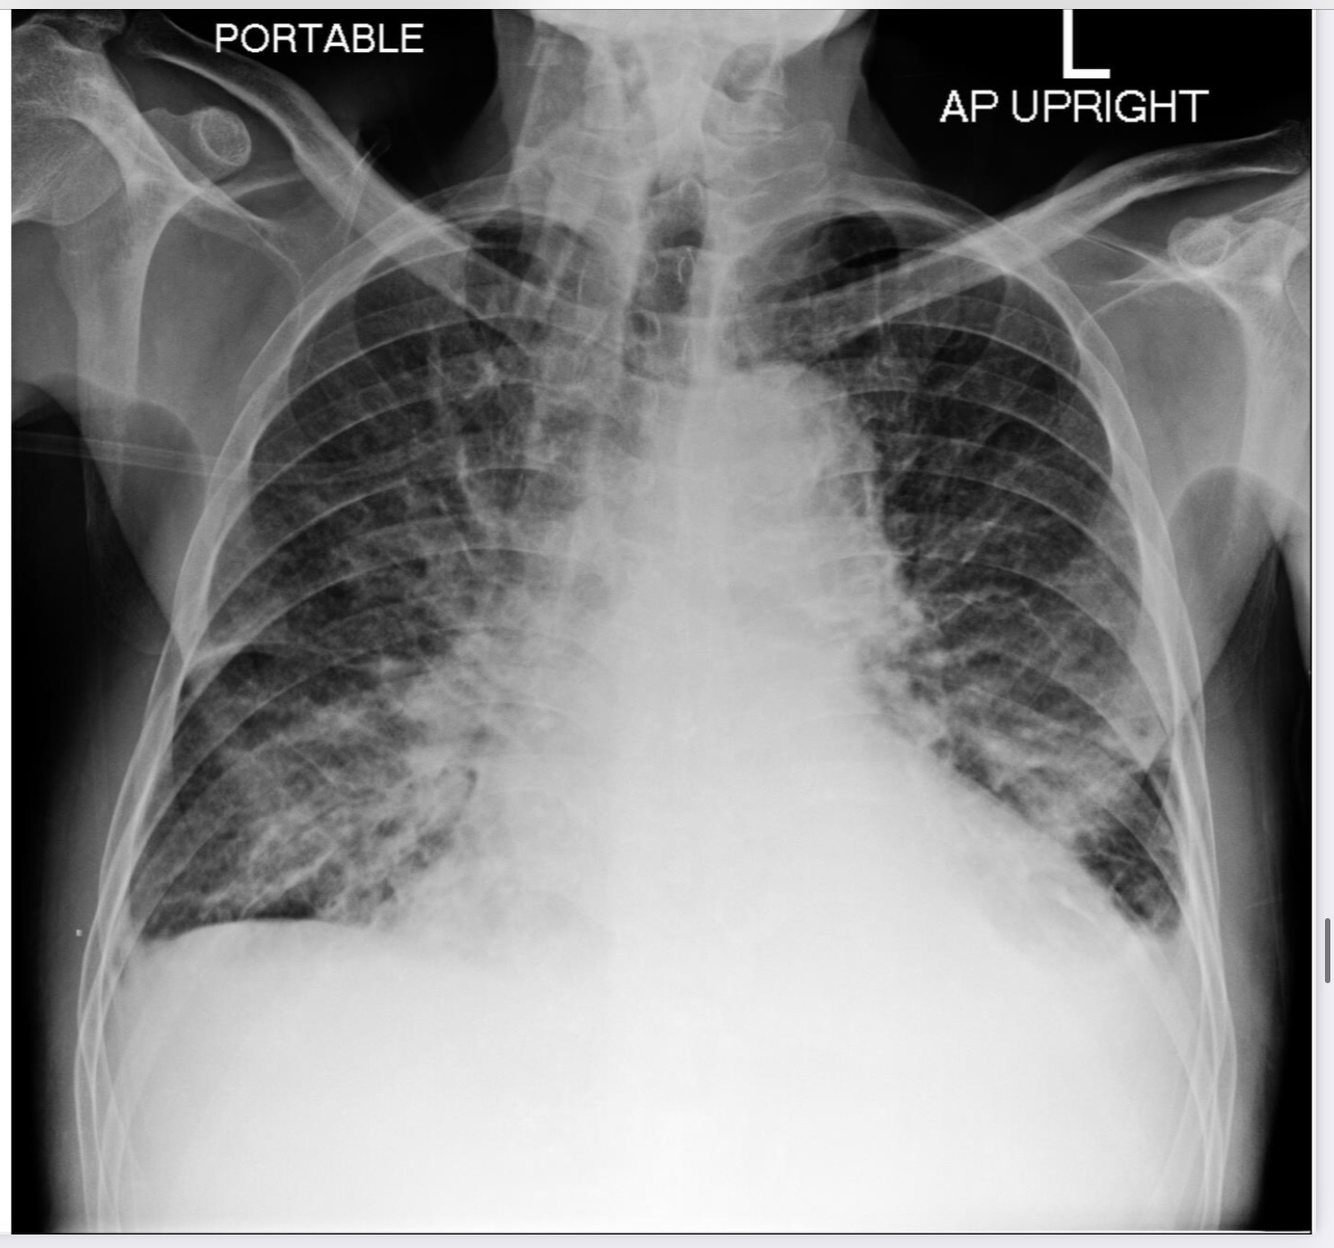

Heart failure

Alveolar oedema

Kerley B lines

Cardiomegaly

Dilated upper lobe vessels